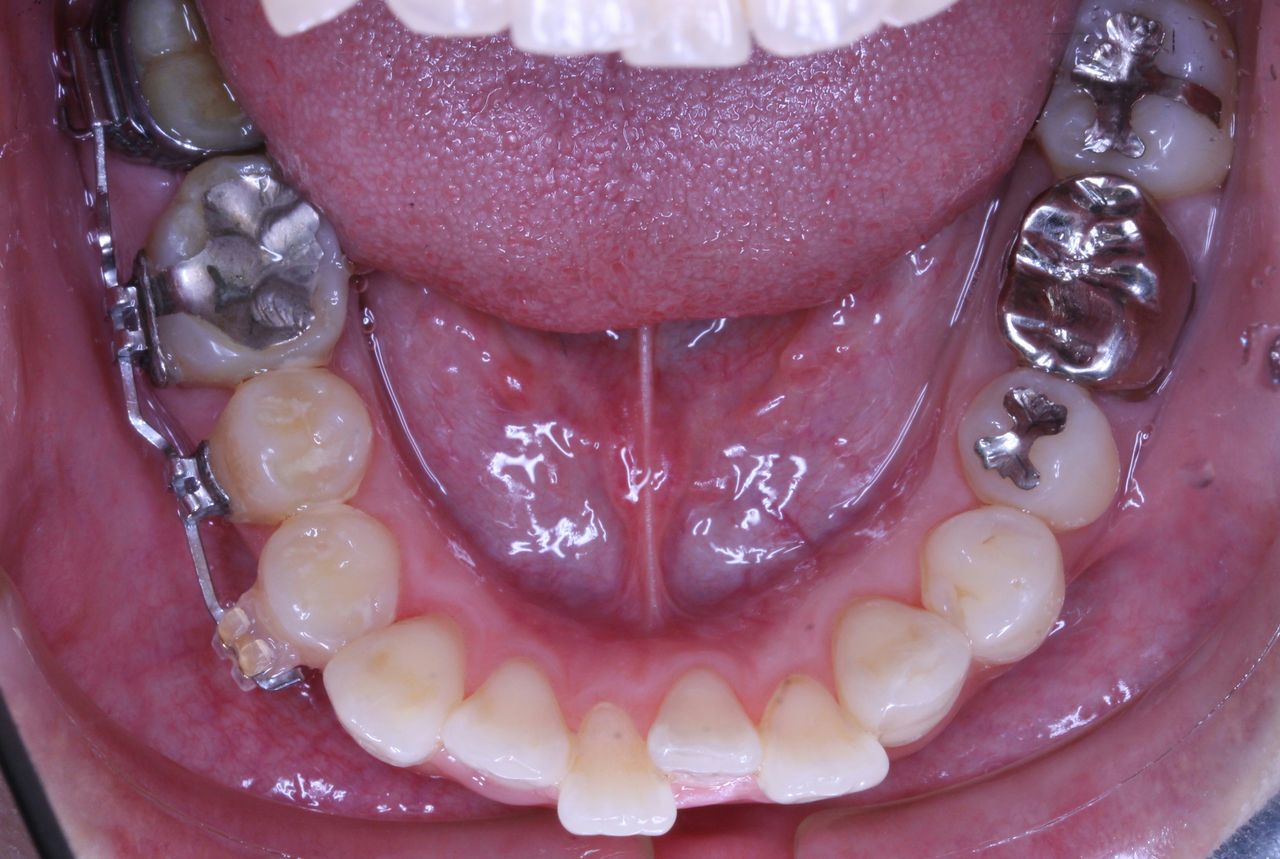

治療開始から3年経過した現在の状況です

上の歯列はどうでしょうか?